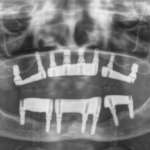

Chirurgia guidata: flusso digitale e scansioni facciali per riabilitazioni complete su impianti

In questo articolo presentiamo la procedura clinica e di laboratorio per l'esecuzione di riabilitazioni a carico immediato con inserimento implantare e pianificazione mediante l'ausilio...